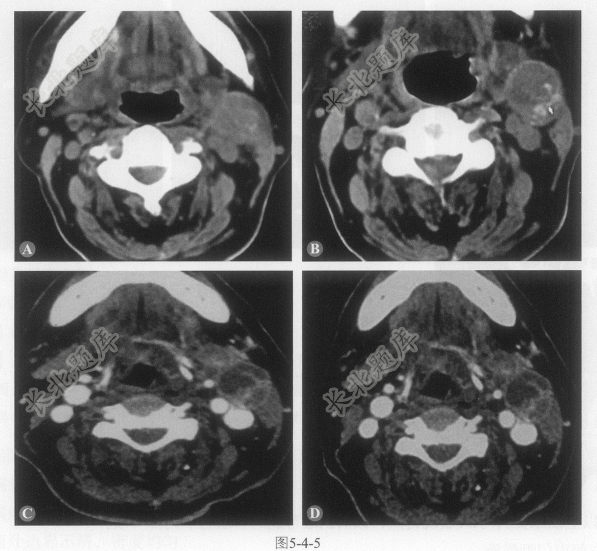

多项选择题4.该病还有图5-4-6,该病诊断为:

A、声门下区喉癌伴左侧Ⅱ区淋巴结转移

B、声门区喉癌伴左侧Ⅱ区淋巴结转移

C、声门上区喉癌伴左侧Ⅱ区淋巴结转移

D、跨声门区喉癌伴左侧Ⅱ区淋巴结转移

E、下咽癌伴左侧Ⅱ区淋巴结转移